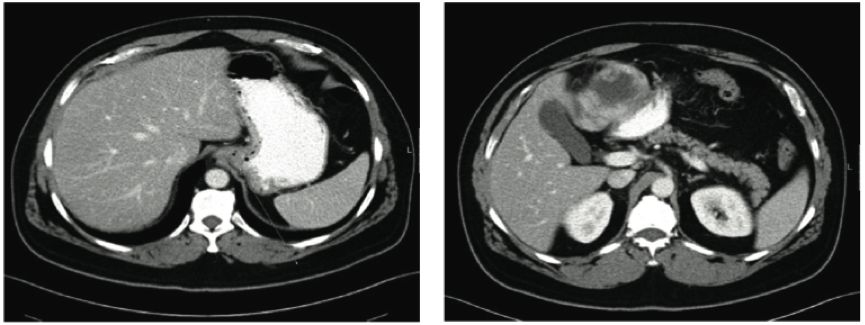

这是一篇关于伊马替尼治疗GIST皮肤不良反应的短篇通讯。1位GIST肝转移的患者术后接受了伊马替尼(格列卫)的治疗,4个月后出现了后背和腹部皮肤的进行性、非瘙痒的鳞屑痂(见附图),皮肤活检提示表皮层的棘层松解,微生物检测阴性,免疫荧光提示细胞间显著IgG沉积伴表皮上层C3沉积,故诊断为伊马替尼相关的落叶型天胞疮,经过暂停伊马替尼治疗并口服强的松龙及咪唑硫嘌呤1个月后,患者症状得以改善。在重新应用伊马替尼后,患者再次出现背部类似皮肤改变,因此予以永久停用伊马替尼并改为舒尼替尼,同时口服强的松龙后,患者皮肤症状得以缓解,在其后2年的随访中,患者未再出现皮肤病变。